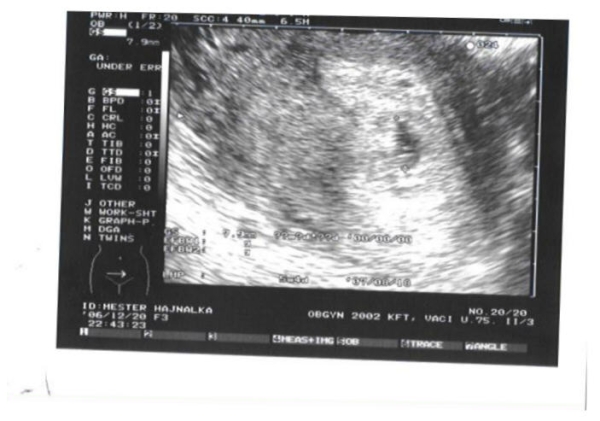

Hajnóca! Megáll az eszem!! Gratulálok sok-sok szeretettel! Így kell ezt csinálni! Azért kicsit bővebben is elmesélhetnéd, mi történT4 Akár priviben is! Imádok sikersztorikat olvasgatni! Vigyázz nagyon magatokra!!!